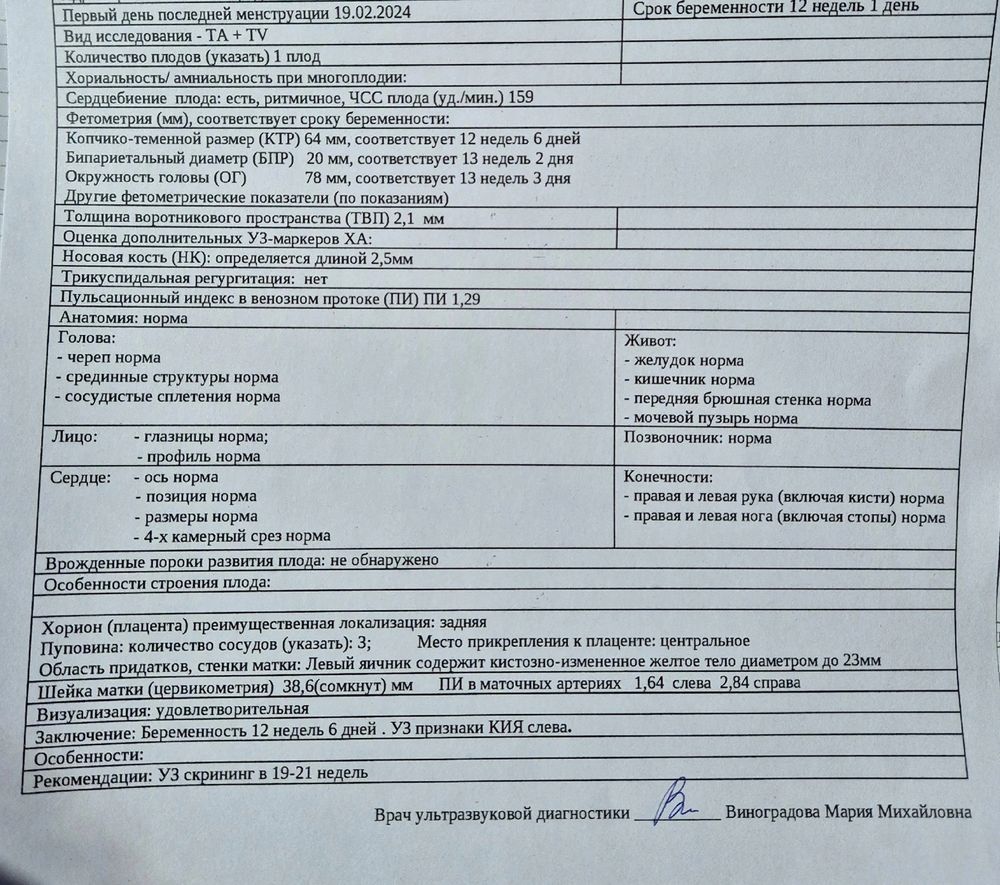

Вот и пролетело время, что уже пройден первый скрининг) А только недавно увидела тенюшку на тесте 🤭

Сказали, что всё хорошо ❤️ кровь сдала. Но, так как в 10 недель был сдан НИПТ, то особо не переживаю. Разве что чуть-чуть) Расти, наш сынок 💫